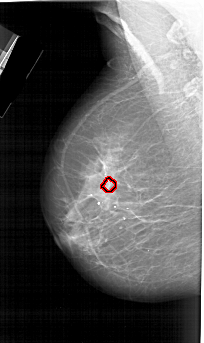

A_1728_1.LEFT_MLO

LEFT_MLO LINES 6511 PIXELS_PER_LINE 3871 BITS_PER_PIXEL 12 RESOLUTION 43.5 OVERLAY

FILE: A_1728_1.LEFT_MLO.OVERLAY

TOTAL_ABNORMALITIES 1

ABNORMALITY 1

LESION_TYPE CALCIFICATION TYPE PLEOMORPHIC DISTRIBUTION CLUSTERED

ASSESSMENT 4

SUBTLETY 2

PATHOLOGY MALIGNANT

TOTAL_OUTLINES 1

BOUNDARY